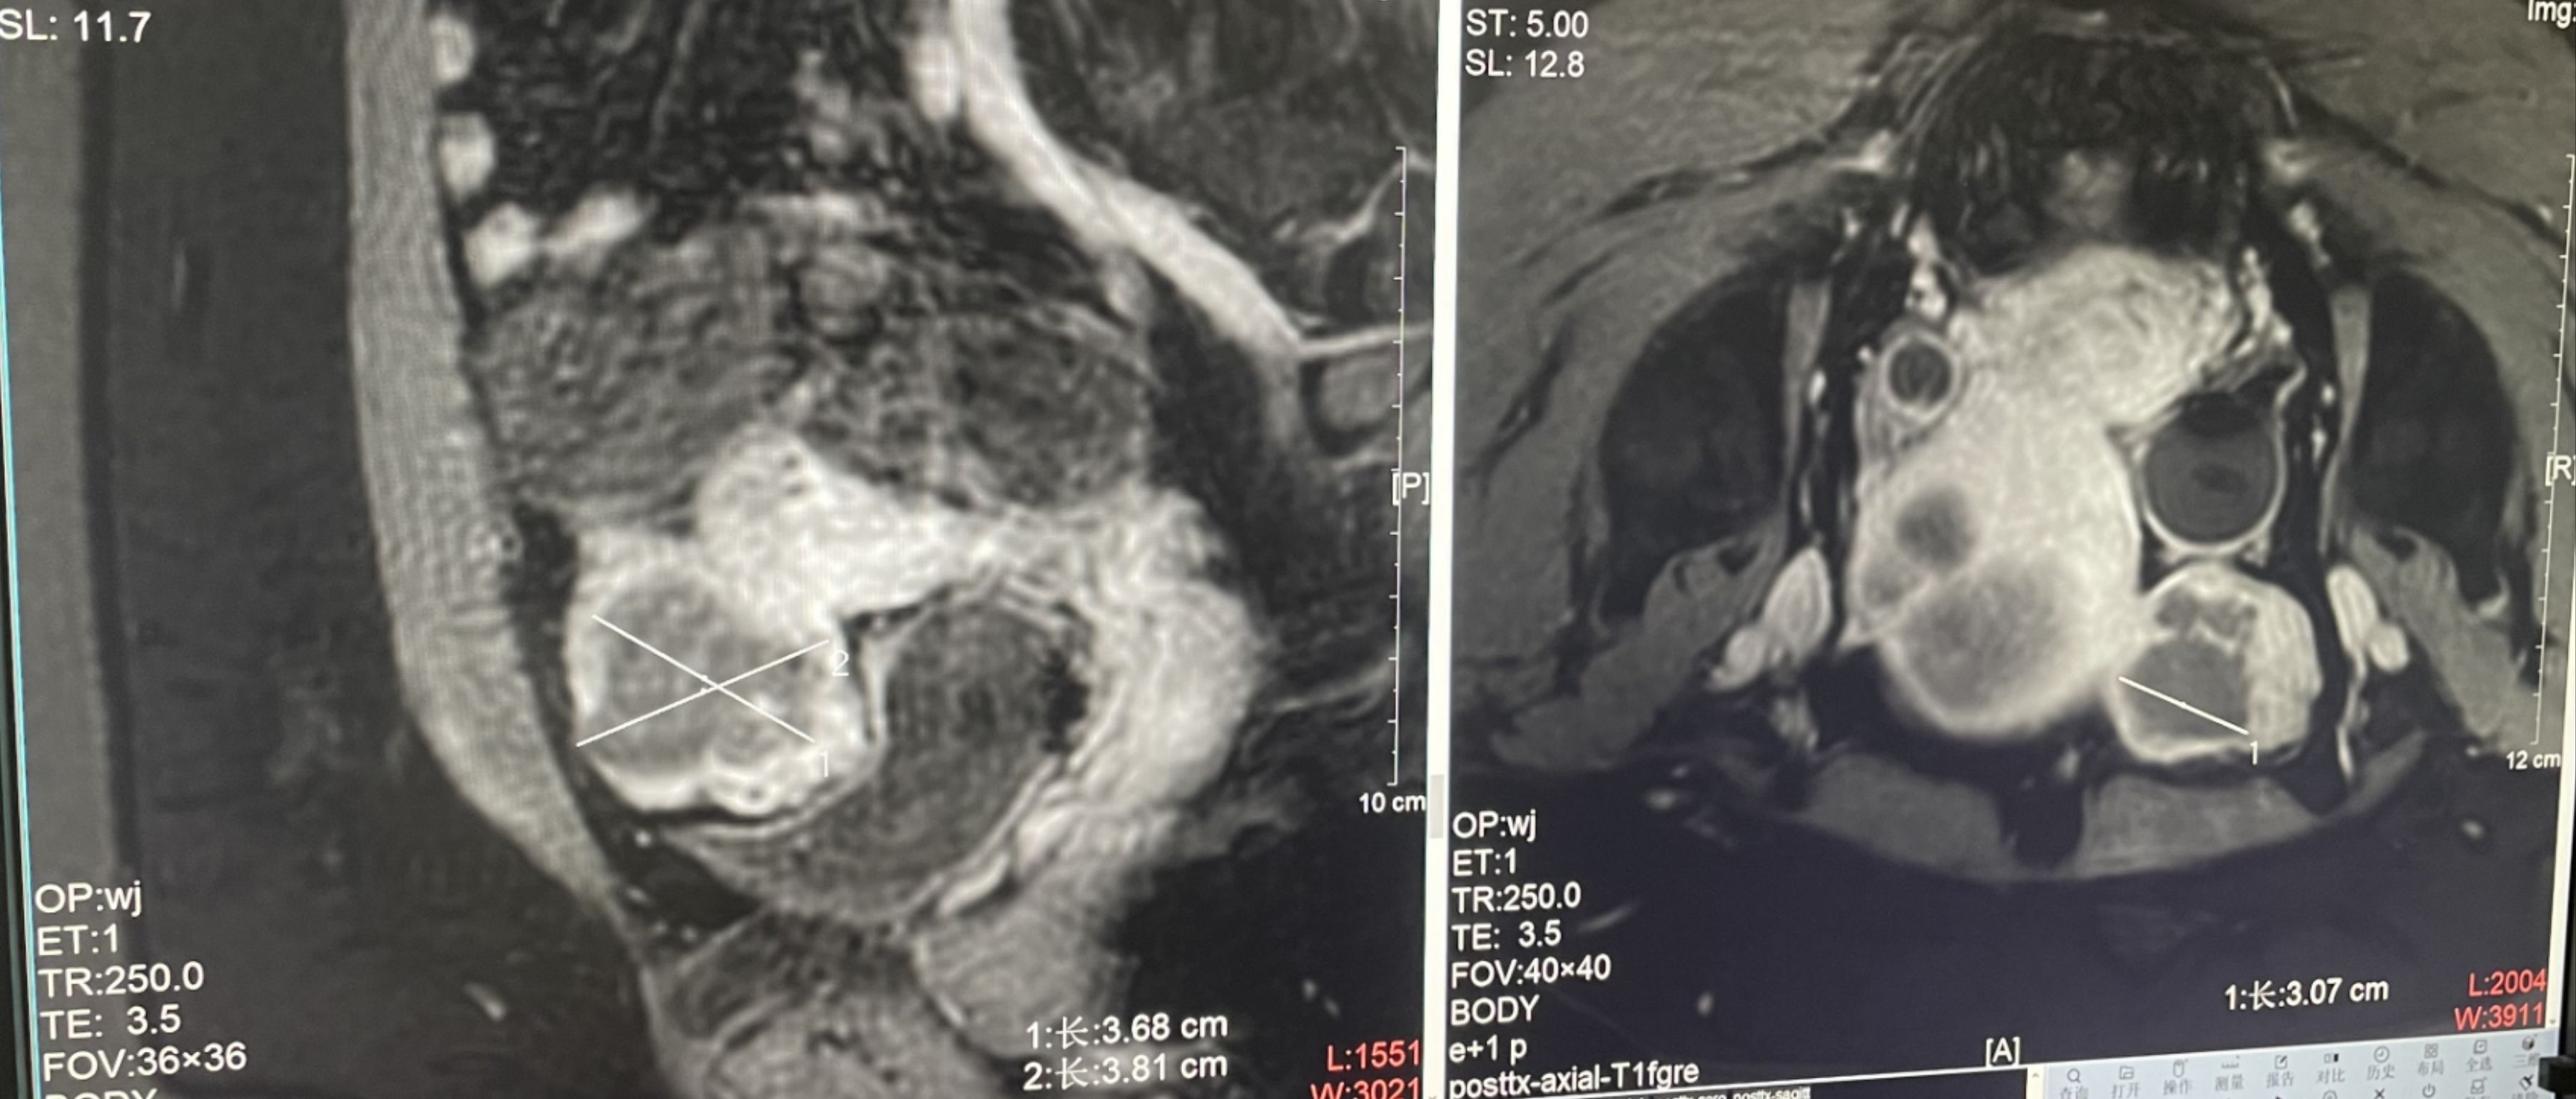

子宮肌瘤

患者信息:女,38

診斷:子宮肌瘤

腫瘤尺寸:約為38*40*42mm

ROT深度:腫瘤的ROT中心距離皮膚62mm

術后評估:術后造影增強圖像顯示消融區(qū)域(右側)與腫瘤區(qū)域(左側)重合度較好,且非灌注區(qū)域連續(xù)且一致。

結論:對該腫瘤具有非常好的消融效果,治療過程中,溫度上升曲線符合預期,每個被治療的靶點240CEM區(qū)域體積較大、外形飽滿、連續(xù)。病灶消融良好,NPV體積比約87.88%。

子宮腺肌癥

診斷:子宮腺肌癥

病灶尺寸:約為40*37*40mm

ROT深度:病灶的ROT中心距離皮膚45mm

術后評估:術后造影增強圖像顯示消融區(qū)域(右側)與病灶區(qū)域(左側)重合度較好,非灌注區(qū)域連續(xù)且一致。

結論:對該病灶具有非常好的消融效果,治療過程中,溫度上升曲線符合預期,每個被治療的靶點240CEM區(qū)域體積較大、外形飽滿、連續(xù)。病灶消融良好,NPV體積比約80.6%。